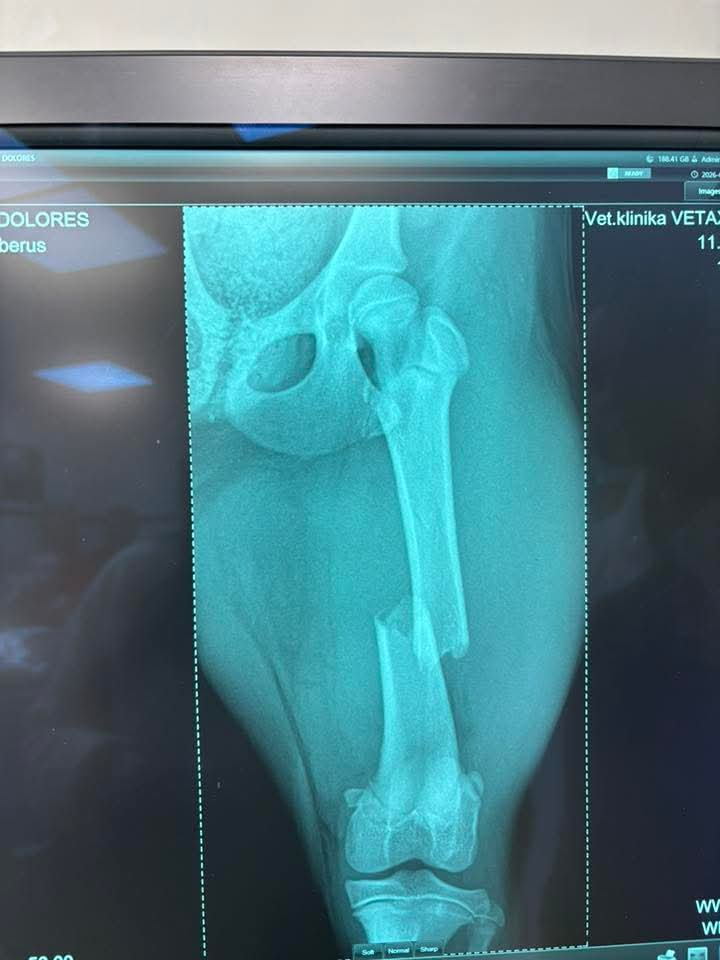

DOLORES

10.3.2026

!!! URGENTNÁ POMOC !!!

Veľmi súrne, urgentne prosíme o pomoc :(

Včera sme prijali toto zranené šteniatko. Fenka zostala na pozorovanie na veterine a zistili že má zlomenú stehennú kosť :(

TERMÍN OPERÁCIE JE ZAJTRA 12:00 U PÁNA DOKTORA ADAMAŤA V TRENČÍNE

CENA OPERÁCIE 600€ :( :( :( Do zajtra musíme peniaze vyzbierať inak nebudeme mať z čoho zaplatiť ...